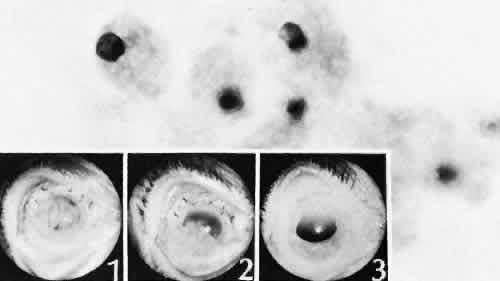

that results in reestablishment of functional ocular anatomy.1–3 The goal of therapeutic intervention in the setting of ocular trauma is to promote the repair process and to allow it to proceed as rapidly as possible and heal as completely as possible without compromising ocular function.4 CELLULAR AND EXTRACELLULAR COMPONENTS The four basic cell types found in wound healing are fibroblasts, vascular endothelial cells, inflammatory cells, and epithelial cells. Specialized cell types that participate in ocular wound healing include corneal endothelial cells, retinal pigment epithelial cells, and Müller cells of the retina. Specific cell populations enter an area of injury under the influence of complex biochemical and biophysical processes involving proteins of the extracellular matrix and the coagulation system. Intracellular proteins, such as tubulin and actin, andmyosin filaments function in cell locomotion. Extracellular matrix proteins, such as fibronectin, laminin, and type IV collagen, orient and regulate cell migration and adhesion.5 Coagulation proteins, such as von Willebrand's factor and plasminogen, alsofunction in regulating the cellular events of healing. Vascular endothelial cells are stimulated to leave their resting state and digest basement membrane, proliferate, migrate, and eventually differentiate under the direction of multiple angiogenic growth factors.6 A wound usually is filled first by a fibrin coagulum. Neutrophils, lymphocytes, and histiocytes (macrophages) enter the wound through fibrin scaffolding to clear necrotic debris and confine toxic or foreign substances. Granulation tissue often is the first type of reparative tissue in wound healing (Fig. 1). Although its composition varies somewhat, small-caliber vascular channels in a delicate collagenous stroma infiltrated by acute and chronic inflammatory cells generally characterize it. This amorphous tissue serves as a template for more definitive repair. Metaplasia is the transformation of a cell from one adult cell phenotype to a second cell phenotype. In advanced wound healing, fibroblasts acquire intracytoplasmic characteristics of smooth muscle cells (myofibroblasts).7 The myofibroblasts are able to contract and bring wound edges together. Vascular endothelial cells proliferate and migrate into the wound from preexisting adjacent vessels. The new “vessel” migrates initially as a solid bulb of endothelial cells. This solid cord of cells will canalize and differentiate into mature arterioles, venules, and capillaries. Fibroblasts grow into the wound in a radial manner but will eventually reorient and secrete collagen along lines of established tissue tension. Epithelial cells are found covering surfaces of tissue. Two distinct types of epithelial cells cover the ocular surface: corneal epithelial cells and conjunctival epithelial cells. Cell replacement is accomplished by stem cells located at the limbus for the corneal epithelium8,9 and at the mucocutaneous junction and possibly throughout the conjunctiva for the conjunctival epithelium.10 Migration and proliferation of surrounding healthy epithelial cells heal surface discontinuity. Apoptosis is a biochemical process leading to programmed cell death. Cell death in apoptosis results from intracellular messages. In necrosis, cell death results from toxic external factors (e.g., hyperosmolality). Apoptosis allows for elimination of entire populations of cells without tissue damage or an inflammatory response.11 Elimination of certain cells is advantageous in embryology (e.g., when scaffolding structures are no longer necessary as with the primary vitreous). In certain neoplastic conditions, however, defects in apoptosis may lead to disadvantageous accumulation of cells. Apoptosis also seems to be highly influential in all types of inflammation, including wound healing. In wound healing, apoptosis may function to control the type and degree of tissue response.12 In the anterior cornea, keratocytes have been observed to undergo apoptosis in response to wounding of the cornea.13,14 Abnormalities of apoptosis may be responsible for such conditions as keloid formation in the skin15 and keratoconus in the cornea.16 Wound healing of highly specialized tissues of the eye has several unique features. CORNEAL HEALING The healing of the cornea is unique relative to other soft tissues, because it lacks blood vessels and because it is lined anteriorly and posteriorly by layers of epithelial-like cells. Epithelial cells of the corneacan produce essential wound healing factors normally produced by platelets.17 Architectural repair is accomplished at the level of the corneal stroma. Abrasions are injuries generally involving only the superficial layer (epithelium) of the cornea (Fig. 2). Abrasions are commonly caused by mechanical injuries or anoxia resulting from contact lens overwear. Some or all of the layers of the surface epithelium are lost, but Bowman's membrane remains intact. After a delay of approximately 1 hour, uninjured epithelial cells at the margin of the wound loosen their intercellular and basal attachments and migrate en masse toward the injured area.18 The shape of the wound margin and the biochemical characteristics of the exposed tissue influence the direction and extent of the migration.19 If the entire corneal epithelium is abraded, migrating epithelial cells derived from the limbal stem cells are able to cover the defect completely within 48 to 72 hours. The epithelium will be much thinner than normal until mitotic division reestablishes normal thickness. Re-formation of epithelial basement membrane may not be detectable for as long as 6 weeks after injury.20 Clinically, the healed wound is transparent. Small defects of Bowman's membrane (Fig. 3) do not heal by fibrous proliferation of the stroma. The defect is filled by proliferating epithelial cells (epithelial facet formation) that reestablish the surface continuity of the cornea. The facet may be seen clinically as a focal, well-demarcated, superficial corneal opacity. A corneal foreign body causes this lesion most often. Penetrating corneal injuries involving at least one third of the stroma (Fig. 4) are covered initially by proliferating surface epithelium that may extend for a considerable distance into the stroma. The extent of corneal epithelial migration is controlled at least in part by contact inhibition of migration once contact with healthy corneal endothelial cells is established.21 Bowman's membrane has elastic properties that tend to pull the anterior margins of the wound apart. Exposure of the relatively dehydrated corneal stroma to tears and blood will cause swelling of the corneal stroma. This swelling of the stroma tends to close the wound. As the stroma heals, new collagen is produced by keratocytes or transformed monocytes. Epithelial cells will regress toward the surface. The repair collagen is different from the native collagen in size and in orientation. The healed wound is densely opaque and obvious clinically, but it may be detected histologically only by the break in Bowman's membrane. Full-thickness wounds of the cornea are associated with retraction of Descemet's membrane and separation of the posterior aspect of the wound (Figs. 5 and 6). Secondary aqueous, a proteinaceous coagulum, may seal the wound posteriorly until healthy surrounding endothelial cells can spread and migrate into the injured area. Mitotic division of the endothelial cells possibly plays an important role in younger patients but probably is not clinically significant in adults. Ultimately, migrated endothelial cells will produce a new Descemet's membrane (Fig. 7).22–25 The portions of Descemet's membrane displaced into the stroma are not resorbed, but remain as the histologic marker of the site of injury. The anterior cellular surface repair of migration and mitosis of epithelial cells is the same as that described for more superficial corneal wounds. The important exception is that with full-thickness injuries, there is a risk of surface epithelial cells migrating along the posterior surface of the cornea or the anterior surface of the iris to the trabecular meshwork. The displaced epithelial cells will cause scarring of the trabecular meshwork and secondary open-angle glaucoma. CONJUNCTIVAL HEALING Conjunctival healing differs from corneal healing because of the presence of blood vessels and a lymphatic system. The conjunctival epithelium heals by migration and mitosis.26 Conjunctival stem cells are thought to originate at the mucocutaneous junction and migrate to the fornix.27 Goblet cells are produced by epithelial progenitors and appear once conjunctival epithelial cell continuity has been reestablished.28,29 The presence of vascular tissue in the substantial propria of the conjunctiva allows for the formation of granulation tissue and scar tissue, as found in soft tissues elsewhere. SCLERAL HEALING The sclera itself does not participate directly in wound healing. Partial-thickness injuries are healed by formation of granulation tissue from the epi-scleral tissue in external wounds or from uveal tissue in internal wounds (Fig. 8). Full-thickness defects of the sclera heal by granulation tissue originating in the episcleral tissue and uveal tract. Mitomycin is used in filtering procedures specifically to prevent the formation of granulation tissue and promote establishment of an aqueous fistula.30 SURGICAL LIMBUS HEALING Currently, there is a trend for the site of the cataract wound to shift from the limbus to the peripheral cornea31 to reduce induced astigmatism32 and to shorten the natural history of cataract wound healing.33 The healing of the wound is similar to that found in central corneal incisions. Healing at the site of a limbal surgical incision involves a combination of the features of repair of the cornea, conjunctiva, and sclera (see Fig. 5). Conjunctival epithelium will heal over an area of granulation tissue originating from the substantia propria of the conjunctiva and the episclera. The granulation tissue seals the wound if the wound edges are well apposed. The remainder of the healing process is similar to the healing of an external scleral wound. Granulation tissue is not formed in the internal portion of the wound because the uveal tract is not involved. The internal wound is healed by endothelial migration and reformation of Descemet's membrane in a manner outlined above for full-thickness corneal wounds.34,35 Because of the lack of blood vessels, the rate of wound healing is slow relative to that of the skin. Whereas an injury to the skin may have regained its tensile strength in 7 to 10 days, injuries to the surgical limbus may require as long as 12 months to regain a stable tensile strength. The tissues of the wound remain structurally weaker than the surrounding uninjured tissue (Fig. 9). The healing of a clear corneal cataract incision proceeds as described above. UVEAL HEALING Wound healing of the posterior uveal tract follows the general principles for healing of vascularized tissue. The iris, however, heals differently. When the iris wound is perpendicular to its circumferential ridges, such as in a typical peripheral iridectomy or iridotomy, the cut edges pull apart. Granulation tissue does not form to close iridectomy incisions probably because of the inhibitory effect of the aqueous flowing through the opening of these small incisions. Iridotomies created by argon laser (Fig. 10) may be anatomically closed by apparent migration of iris pigment epithelium.36,37 LENS HEALING Proliferation and fibrous metaplasia of the lens capsular epithelium (Fig. 11) may close small rents through the lens capsule. After maturation of the fibrous tissue, the most superficial epithelial cells will form a new lens capsule. Most wounds to the lens, small and large, result in cataracts. Small wounds, however, may result in tiny focal opacities.38–39 Lens epithelial cells undergo fibromyoblastictransformation when stimulated by injury. The transformed cells are able to produce type I and type III collagen and glycosaminoglycans.40 This is the fundamental process resulting in opacification of the posterior lens capsule after extracapsular cataract extraction or phacoemulsification.41 Apoptosis (programmed cell death) also plays a role in the formation of secondary cataracts.42 RETINAL HEALING Wound healing of the neurosensory retina follows the principles of wound healing. There is an initial removal of all necrotic tissue by phagocytosis followed by proliferation of cells to form a chorioretinal bond. The healing, however, is modified in most instances by the lack of participation by the blood vessels.43–45 Astrocytes from the neurosensory retinaproliferate from the peripheral viable tissue into the wound and downward into the area of the subretinal space (Fig. 12). Retinal pigment epithelial cells from the peripheral viable tissue undergo fibrous metaplasia and proliferate upward into the area of the subretinal space. When the two proliferating cell types unite, a tight chorioretinal bond is formed. Increased retinal adhesiveness has been estimated to be 140% of the normal degree of adhesiveness 2 weeks after photocoagulation.46 Retinal holes may heal spontaneously if supported by an intact vitreous base or if located adjacent to the retinal pigment epithelium (Fig. 13).47,48 For the retinal pigment epithelium to differentiate, it must be in contact with overlying retinal pigment epithelium.49 Choriocapillaris repair from a photocoagulation wound of the retina appears to proceed in a manner similar to that of repair of capillary thrombosis in other tissues.50 The vascular repair process may not reproduce the lobular architecture of the native choriocapillaris.51 The choriocapillaris may regenerate in areas of restored retinal pigment epithelium.52 Proliferative vitreoretinopathy is an expression of abnormal retinal wound healing.53 Interruption of Bruch's membrane may allow the ingrowth of fibrovascular tissue from the choroid into the subretinal space, resulting in a modified granulation wound healing process and subretinal scarring.54 |